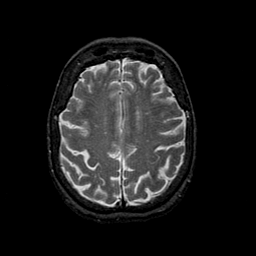

Normal aging, overlay -- Slice #37

[Home][Help][Clinical] Slice 37